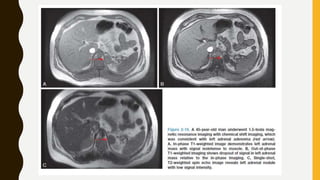

Adrenal Adenoma

• Adrenal adenomas are characterized by assessing the lipid content within cells. CSI

• CSI obtains images “in-phase” (IP) and “out-of- phase” (OP) with regard to the water

• In the OP imaging, the TE is set to cancel the signals obtained, thus the

• The next step is to compare the two data sets (IP and OP) obtained to determine if

• The loss of signal on CSI is 92% sensitive and has a limited specificity of 17% for